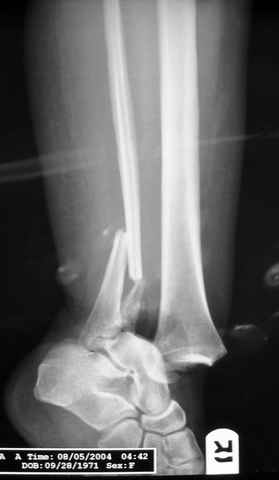

Pilon fracture:

-Появляется ориентир и остов, на чем можно строить восстановление, почему сперва малоберцовую, впервые обьяснили и описали (Pylon type and Ankle fractures) в середине 50х Rienau и Gay.

Восстановливая длину и ротацию малоберцовой кости, затем относительно легче произвести реставрацию остальных элементов перелома дистального эпиметафиза болшеберцовой кости.

где исследования на трупах показали, что малоберцовая кость участвует в стабильности голеностопного сустава, поддерживая наклон тарана (talar tilt) за счет связок. После ознакомления работой Ramsey в ортопедию ввели термин "при переломах голеностопного сустава смещенная

таранная кость следует за малоберцовой костью" т.е. связка не рвется, а тянет таран за собой, поэтому восстановление малоберцовой кости в

первую очередь, затем остальных элементов - стал классическим при лечении данной патолгии. Латеральная колонна (столб), дистальный

конец малоберцевой кости, к нему прикрепляется латеральный суставной фрагмент дистального эпиметафиза большеберцовой кости (как на снимке)

и таранная кость, которые при репозиции малоберцовой кости репонируются автоматически.

Из работ Ramsey and Hamilton, Yablon et., укорочения на 1мм

малоберцовой кости, уменьшает на 42% контактную поверхность между

малоберцевой и таранной кости, которое в свою очередь приводит к

увеличению давления на остальные части суставной поверхности, что

является предпосылкой раннего артроза.

The unsatisfactory clinical results sometimes associated with slight widening of the ankle mortise and 42% reduction in the area of contact

between the tibia and talus with one millimeter of lateral displacemet emphasize the importance of restoring the normal roentgenographic relationship of the talus to medial malleolus after ankle

injures. Since the stress per unit area increases as the total area decreases, a decrease in contact area may be a factor contributing to a poor result after ankle or dislocation when talar displacement is one millimeter or more.